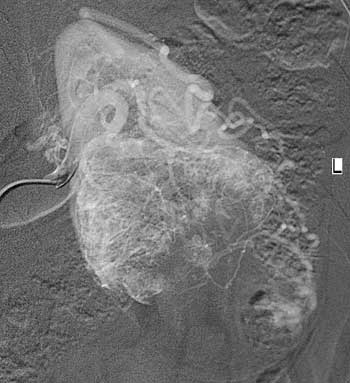

Рис. 6. Рак левой почки. Т2N0M0. Мелкая радиально расположенная от периферии опухолевая васкуляризация с центральной аваскулярной зоной, что характерно для VI типа васкуляризации.